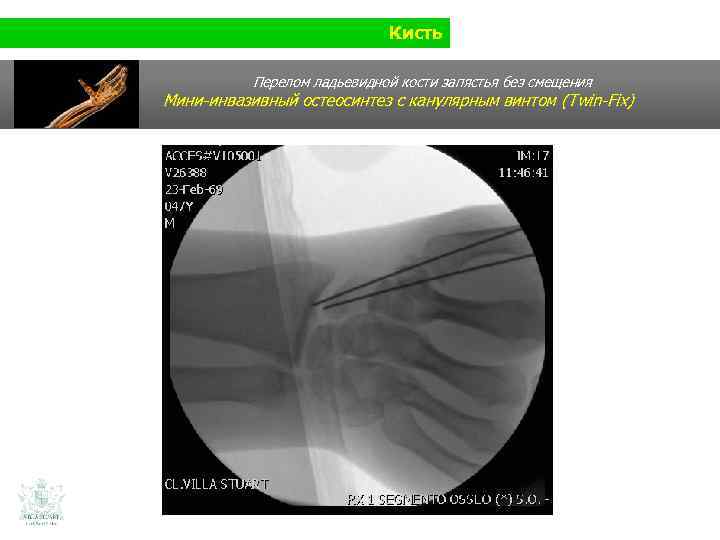

Кисть Перелом ладьевидной кости запястья без смещения Мини-инвазивный остеосинтез с канулярным винтом (Twin-Fix)